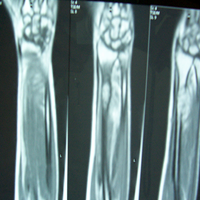

Case:1 GCT L/E Radius

Pre-Op